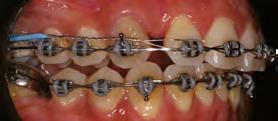

52 | SONRIENDO AL FUTURO

Tratamiento ortodóncico en paciente adulto tratado con extracciones de primeros molares permanentes. Reporte de caso

Tratamiento ortodóncico

en paciente adulto tratado con extracciones de primeros molares permanentes. Reporte de caso